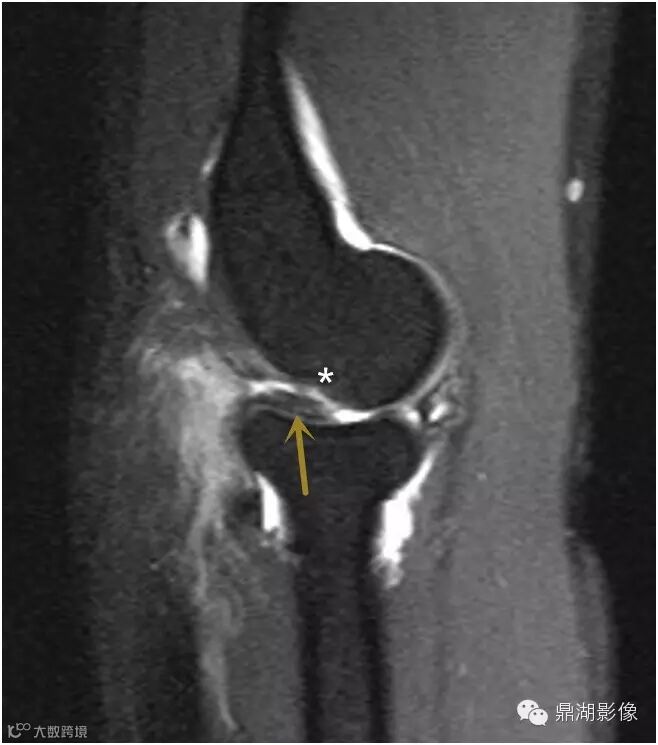

抑脂序列冠状位及矢状位T2WI显示在后外侧肱桡关节间隙内增厚的滑膜皱襞隆起并折叠(箭头)。

皱襞内可见高信号影,测量超过3毫米的厚度,并覆盖了几乎一半的桡骨头关节面。并可见易被误认为是肱骨小头缺损的正常肱骨头(*)。